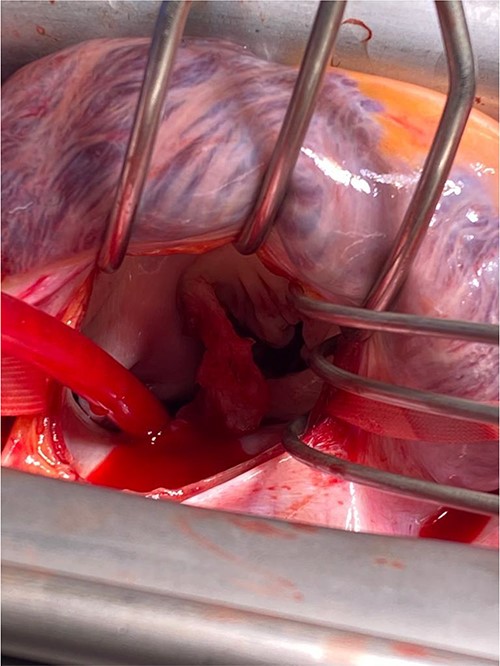

A CTPA was undertaken on Day 2, which excluded pulmonary embolism but confirmed bilateral peri-hilar consolidation and pleural effusions consistent with pneumonia. However, her pulmonary artery was dilated at 32 mm indicative of potential heart failure. On Day 5 of her ICU stay, a transthoracic echocardiogram was undertaken that revealed there to be severe mitral regurgitation including a mobile echogenic mass attached to the underside of the anterior mitral valve leaflet consistent with a vegetation (Figs 1 and 2).

Pre-operative TTE with Doppler depicting mitral valve with vegetation (labelled).

Intra-operatively, femoral–femoral bypass was established and a 3 cm windsock vegetation was found with a 1.5 × 1.5 cm hole at the aortic inlet on the annular junction. The vegetation travelled from the LV to LA as shown in Figs 3 and 4. The vegetation was excised and the valve debrided, which resulted in moderate regurgitation from severe. Hence, a further 26 mm Physio II ring was placed resulting in no mitral regurgitation. The excised vegetation is shown in Fig. 5 and the post-op TTE images are shown in Figs 6 and 7.